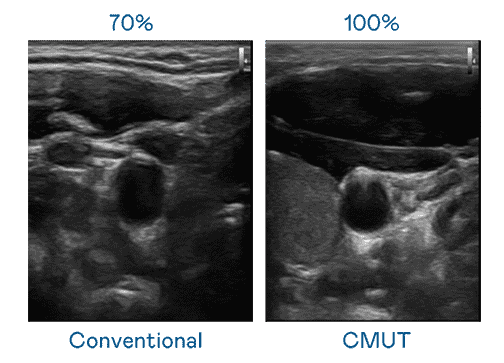

CMUT 技术是一种用电容式微机电元件来产生超音波讯号的技术。。。与传统 PZT 压电式技术相比,,,,CMUT 频宽增加 30%,,,,更宽频的超音波讯号让影像解析度大幅提升,,,,是实现高影像品质医疗超音波扫描、、、促进精准医疗发展的关键技术。。

大频宽带来超清晰影像

超音波影像的解析度高低,,,,首先取决于探头能发出的讯号频宽。。尊时凯龙 CMUT 可提供高清晰的超音波讯号,,,,提供高频宽、、高灵敏度、、、、影像纹理细节更高的超音波影像,,,,协助医护人员缩短影像判读时间及利用精准的医疗影像进行诊断。。